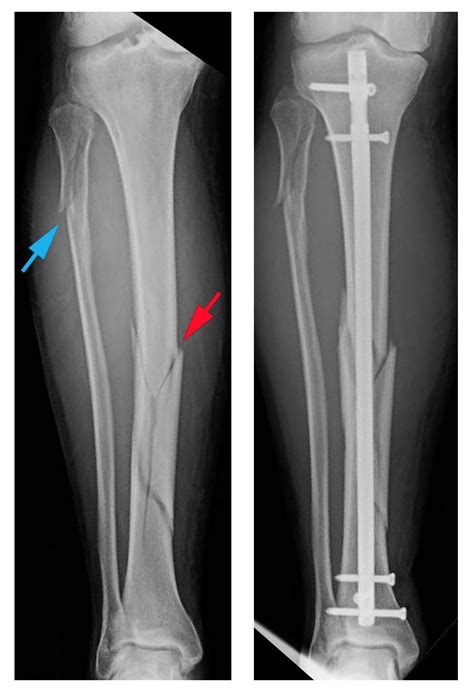

Spiral Fracture: Healing Time, Tibia, and Fibula